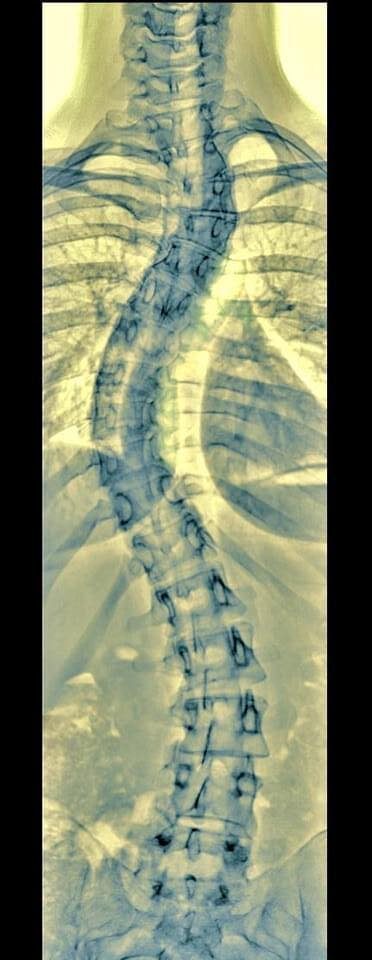

right below it is this image of my spine. [fb]

He draws my pose from behind, using my curved Xray as dragon tattoo inspiration, the crooked angled lines like my crooked spine, the green tint. My photo logo at the bottom right provides the dark red of the ink. [IG]